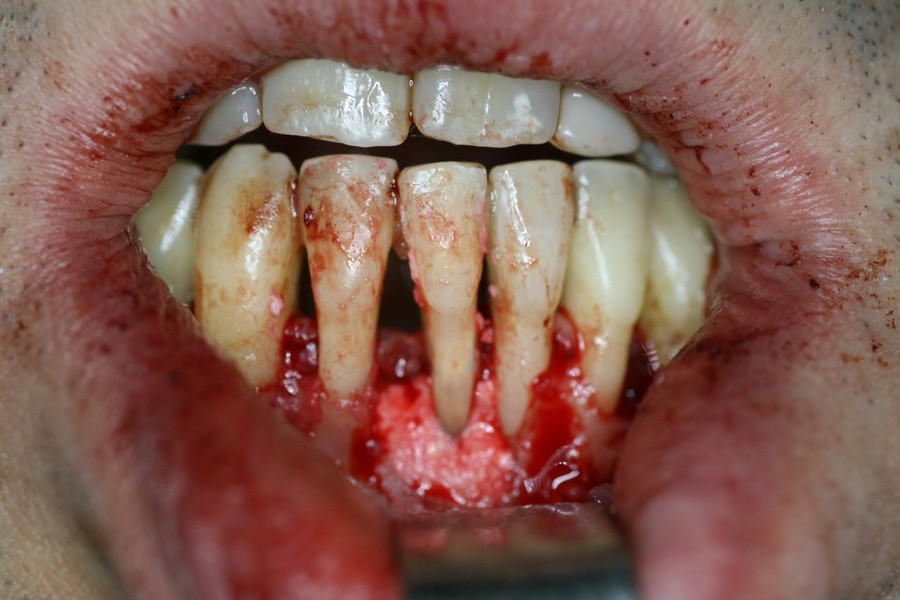

Rigenerazione Gravi difetti parodontali

Rigenerazione difetto parodontale di un canino inferiore con materiale eterologo

rigenerazione grave difetto parodontale a carico del 46

rigenerazione grave difetto parodontale a carico una intera emiarcata